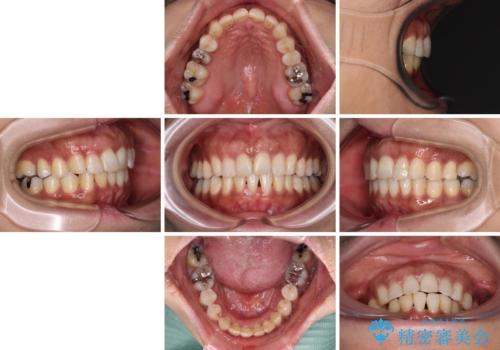

- 上下前歯のデコボコ改善をインビザラインにて行いたいとのことで来院された患者様です。

インビザラインをご希望のことで、IPR(歯と歯の間を削る)などによりスペースを獲得して、排列していくこととしました。

骨格的に上下顎が左右にずれていたため、正中位置は現状を維持したまま歯列不正を解消していくことになります。

なかなか装着時間が守れず、後戻りを繰り返しながら治療を進めたため、インビザライン治療期間期限ギリギリの5年弱の期間を要しました。